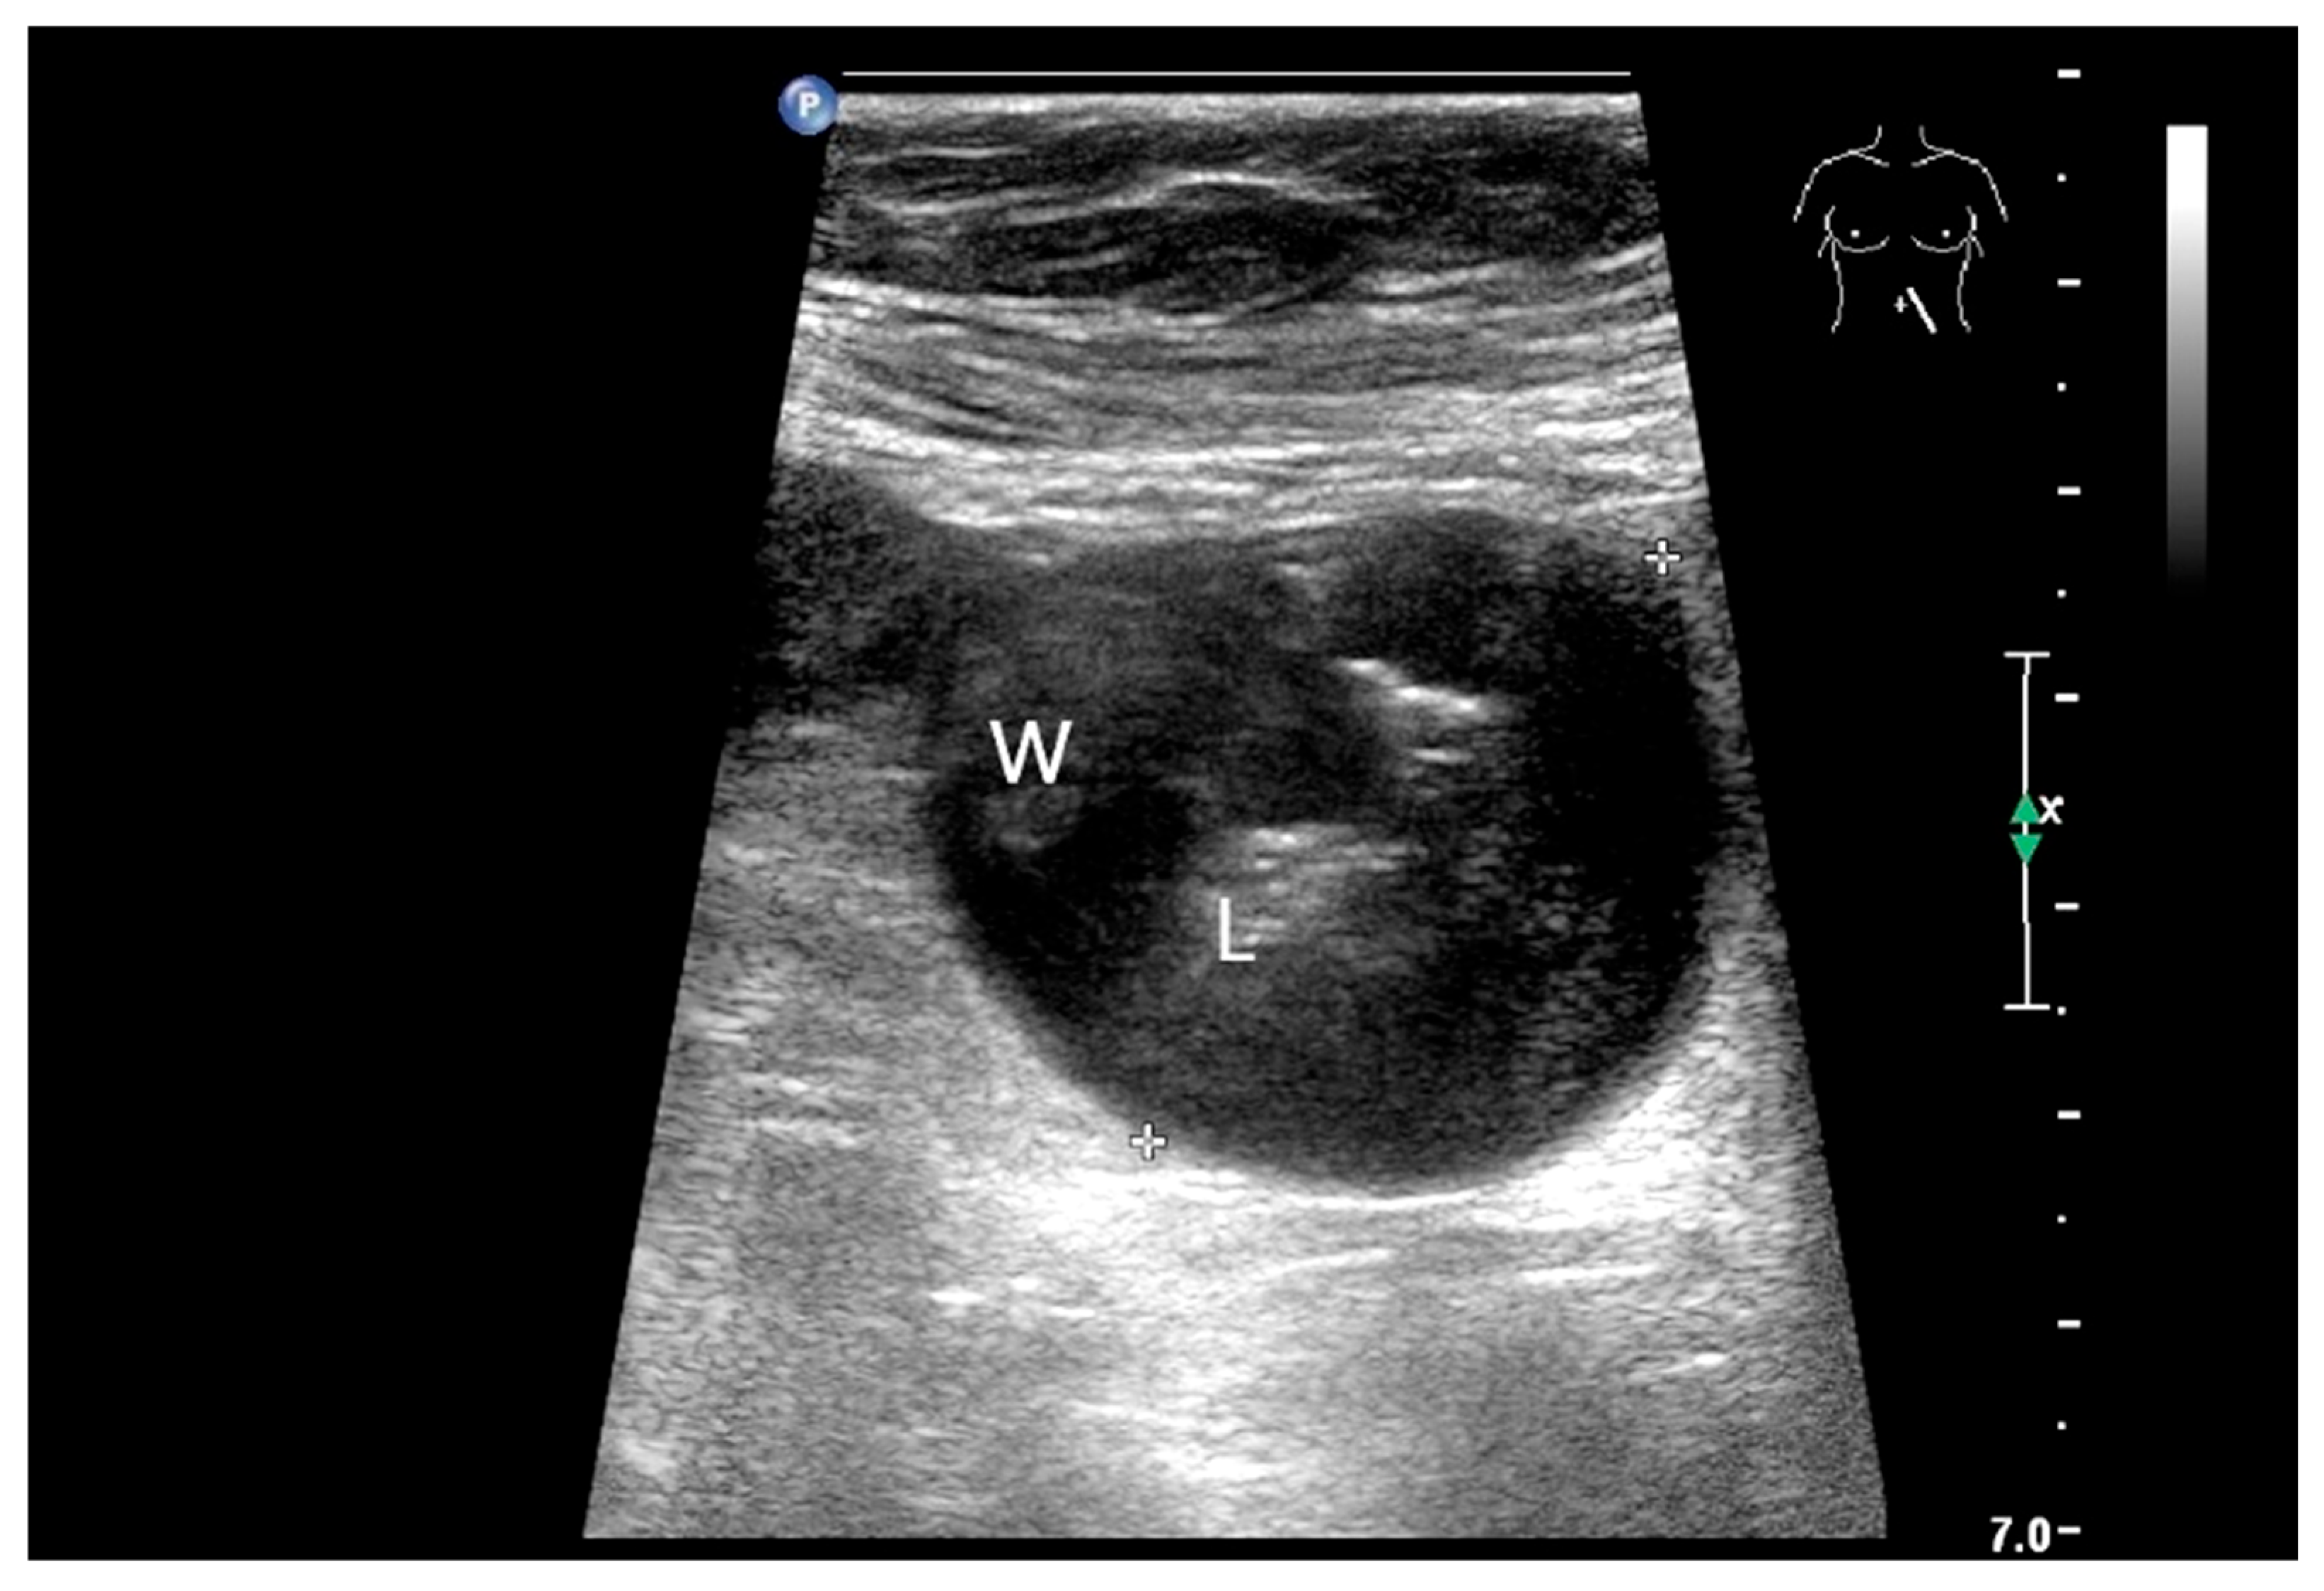

Metastases of other tumors can occur in the small intestine. These include cutaneous melanomas, breast carcinomas, lung carcinomas, renal cell carcinoma, thyroid cancer, ovarian tumors, testicular tumors and head and neck squamous cell carcinoma [4,143,144,145,146,147,148]. In a study of more than 5000 patients, melanomas (66% of all small bowel metastases) were the most common secondary small intestine tumors [32]. In a study of 193 malignancies in the small intestine over a period of 20 years, 5.7% were metastases [146]. The metastases were located in both the jejunum and ileum [146]. Small bowel metastases of head and neck squamous cell carcinoma were mostly located in the ileum (58%), also jejunum (25%), and less frequently in the duodenum (15%) [143]. Clinical manifestations of small intestine metastases are gastrointestinal bleeding, abdominal discomfort up to acute abdomen in connection with intestinal lumen obstruction and also intussusception [146]. They manifest themselves as wall thickenings or intramural nodules in the wall of the small intestine (Figure 18 and Figure 19).

Figure 18.

Small intestine metastasis of a malignant melanoma (between the markers). Significant hypoechoic wall thickening (W) with narrowed lumen reflex (L) and lumen obstruction.